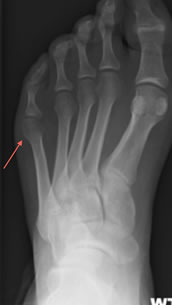

This is a prominence of the base of the 5th toe/little toe. The prominence is the head of the 5th metatarsal bone found just at the base of the little toe on the outside border of the foot.

The name originates from the typical seating posture seen by a Tailor when working. Often no cause is found however tighter footwear can exacerbate problems, foot shape can predispose people to discomfort, if you have a particularly widened forefoot or an unusually “bowed” 5th metatarsal bone on X-Ray.

The clinical features as discussed above in addition to typical X-Ray findings diagnose the problem.